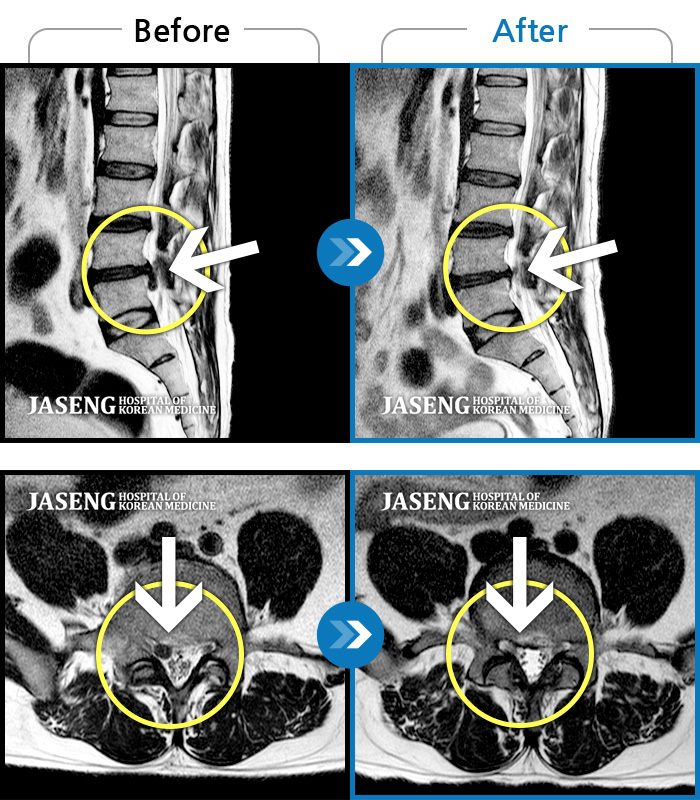

Before

After

처음 내원시 허리 통증이 심하여 일상생활에 불편감이 있으신 환자분이셨습니다.

2023.10.03 ~ 2025.03.22